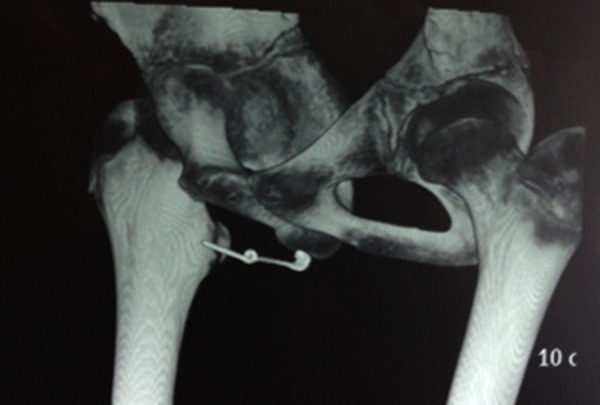

14-летний мальчик обратился в амбулаторное отделение нашей больницы с жалобами на боль в промежности и жгучую боль во время мочеиспускания. При детальном обследовании и из истории болезни мы узнали, что он вставил английскую булавку в мочеиспускательный канал с целью сексуальной стимуляции. Ранее у него не было в анамнезе каких-либо серьезных психических заболеваний. Его общее состояние было хорошим. При клиническом обследовании у мальчика была сильная локальная болезненность и что-то прощупывалось в области промежности. Анализ мочи выявил небольшое количество лейкоцитов и 2-3 эритроцита в поле зрения. Обычный рентгеновский снимок левой передней части таза, выполненный наискось, показал рентгеноконтрастное металлическое инородное тело (открытая английская булавка) в плоскости мягких тканей спереди-снизу от лобкового сочленения.

Figure 1. Рентгеновский снимок таза показывает рентгеноконтрастное металлическое инородное тело (открытая английская булавка) в плоскости мягких тканей кпереди от лобкового сочленения.

Figure 4. 3D реконструированное КТ показывает сверхплотное металлическое инородное тело (открытая английская булавка) кпереди от лобкового сочленения.